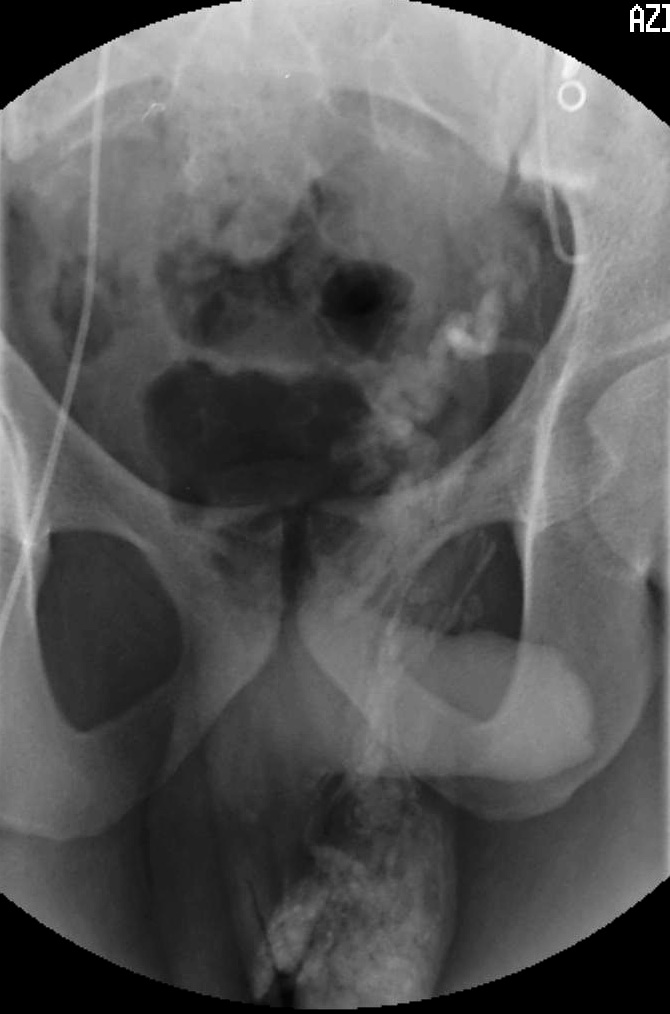

麻醉和入路 经皮栓塞治疗在静脉麻醉和镇静下进行,除非患者有严重的出血倾向或对造影剂有严重过敏反应史,一般均可在门诊完成。入路包括经股静脉入路,经颈静脉入路,经贵要静脉入路。二十世纪70年代最先报道用硬化剂代替金属圈。Formanek 最早在1981年提出的经颈静脉途径【Formanek A,1981】,由于其进入睾丸静脉的易行性和安全性目前已获得使用。据Morag报道【Morag B 1984】,通过颈静脉对右侧睾丸静脉进行栓塞的成功率较股静脉途径更高,前者成功率为89%,而后者则为62.5%。Kuroiwa报道通过贵要静脉的栓塞治疗比股静脉途径成功率更高【Kuroiwa T 1991】。最近,有数位作者报道,在用气囊或金属圈经股静脉途径进行栓塞时,可使用引导导管或同轴系统作为辅助。 栓塞水平的选择 由于分支血管存在变异,静索静脉曲张的栓塞治疗可以在内侧静索静脉的几个不同平面进行。未栓塞的交通支,特别是如果有较大的分支,可能会很快引起复发而且几乎没有临床改善,而较小的分支可能会随着时间逐渐增大,从而导致复发。Fobbe评估了在不同部位利用硬化剂材料对睾丸静脉进行阻断治疗的成功率【Fobbe F, 1987】。治疗后3个月,在静脉的近侧进行阻断,其技术成功率为68%,而在静脉末梢即靠近腹股沟环处进行阻断,由于消除了很多分支血管,成功率可达82%。 栓塞步骤 静索静脉曲张栓塞治疗的步骤是,首先对患者进行静脉镇静,如咪哒唑仑盐酸盐和芬太尼,以及硝苯地平(10mg)舌下含服,以减少可能引起的睾丸静脉痉挛。然后,用微血管穿刺装置(Cook, Inc)中的21号针进行颈内静脉穿刺,穿刺成功后置换套装置中的套管,通过套管将0.038英寸引导丝(Terumo)进入下腔静脉。插入长30cm、口径6 French的导管套(Medi-Tech),并通过导管套将5.5 French H1H(Cook, Inc)或5 French Bernstein导管(Medi-Tech)插入肾静脉,通常还需要成角的亲水导丝(Terumo)协助。 如果采用右侧股总静脉途径,则用5 French直导管(Cook, Inc)和尖部弯曲导丝(Cook, Inc)进入左侧睾丸静脉,用5.5 French Simmons 3导管(Cook, Inc)进入右侧睾丸静脉。较新的技术使用引导导管较尖部弯曲导丝更多。

患者处于反Trendelenburg位置,进行左肾静脉造影,以发现睾丸静脉的返流。将导管插入左肾静脉,进行睾丸静脉造影以发现睾丸静脉的返流,以及体循环和门静脉系统的分支显像。使用护罩或充分的平行光,来尽量减少睾丸的暴露。无需对静索静脉曲张直接照相,这样可能会增加性腺接受的放射性剂量。导管进入腹股沟管的部位,因此应避免经阴囊照相。在试图阻断所有可能会引起复发的分支时,推荐使用5-mm和8-mm Gianturco圈(Cook, Inc)(由于其放置容易而且价格便宜)。必须格外小心,避免金属圈的展开部分进入肾静脉或选择直径太小的金属圈,尤其在静脉痉挛时,这样可能会导致金属圈入肺。如果出现静脉痉挛,给予1ml 硝酸甘油液(100µg/ml)缓解痉挛。

左侧睾丸静脉栓塞后,可以将导管选择性插入右侧睾丸静脉。右侧精索静脉曲张发生率一般认为是5-9%,各种文献报告在30-80%之间【Kunnen M 1981 Morag B 1985 Formanek A 】。如果功能正常,则无需进行栓塞。如果功能不全,可以进行与左侧类似的栓塞。手术后4-6小时患者即可出院。应告知患者24小时内避免体力劳动。手术后的症状包括睾丸和后背疼痛,并可能出现低热,可以用非甾体类抗炎药治疗。